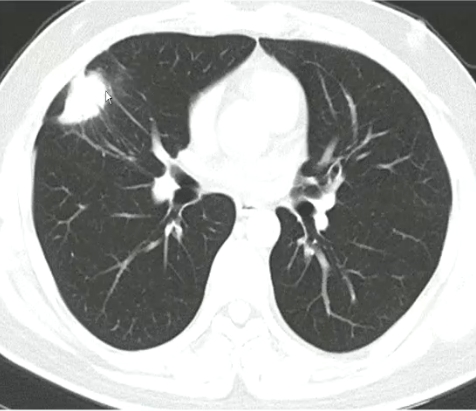

肺隐球菌感染-肿块肺炎型

●主要累及肺野中带和(或)外带

●其长轴常与胸膜平行

●收缩征常见,邻近胸膜间断受累为主

●病灶密度多较均匀

●其内支气管充气征常见

●周围可见多少不等的磨玻璃影或结节影